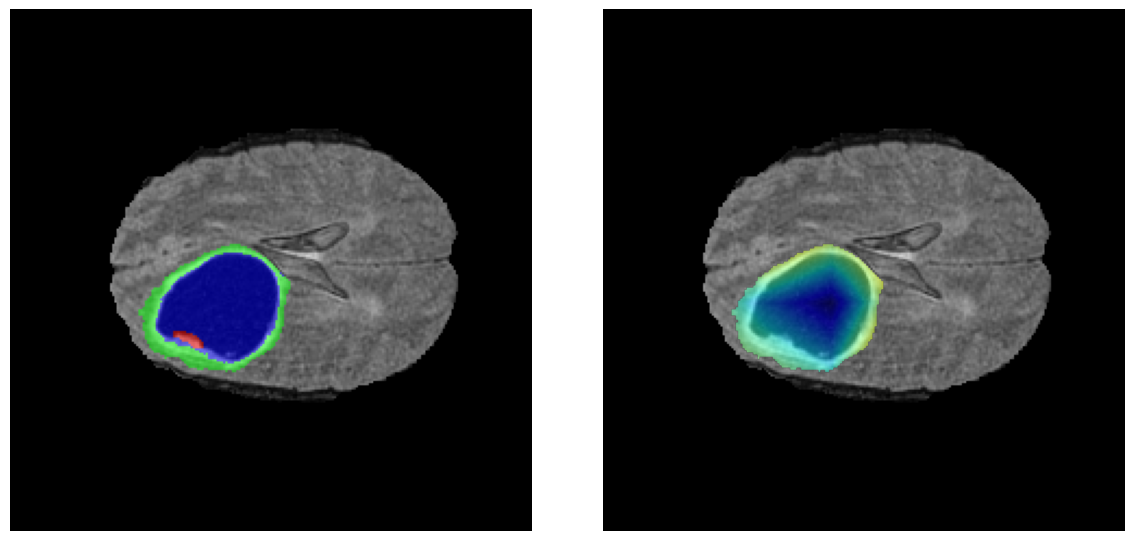

Mapas de Explicabilidad (Grad-CAM++)

Visualización de las regiones de atención del modelo que validan su razonamiento clínicamente relevante

Ejemplos HGG - Atención en Núcleo Necrótico y Tumor Realzado

HGG Grad-CAM++ 1 HGG Grad-CAM++ 2 HGG Grad-CAM++ 3 HGG Grad-CAM++ 4 HGG Grad-CAM++ 5 HGG Grad-CAM++ 6

Los heatmaps muestran que el modelo concentra su atención en las regiones de Tumor Realzado (rojo) y Núcleo Necrótico (azul), características patológicas clave de los gliomas de alto grado.

Ejemplos LGG - Atención Difusa en Edema Peritumoral

LGG Grad-CAM++ 1 LGG Grad-CAM++ 2 LGG Grad-CAM++ 3 LGG Grad-CAM++ 4 LGG Grad-CAM++ 5 LGG Grad-CAM++ 6

Para casos LGG, la atención del modelo es más difusa y se concentra principalmente en la región de Edema Peritumoral (verde), consistente con la naturaleza más infiltrativa y menos agresiva de estos tumores.

El análisis Grad-CAM++ reveló que el modelo desarrolla automáticamente la capacidad de localizar las regiones tumorales. Para casos HGG, la atención se alinea fuertemente con las regiones de Tumor Realzado (ET) y Núcleo Necrótico (NCR). En contraste, los casos LGG muestran atención más difusa, principalmente concentrada en la región de Edema Peritumoral (ED), lo cual es consistente con la patofisiología conocida de los gliomas.